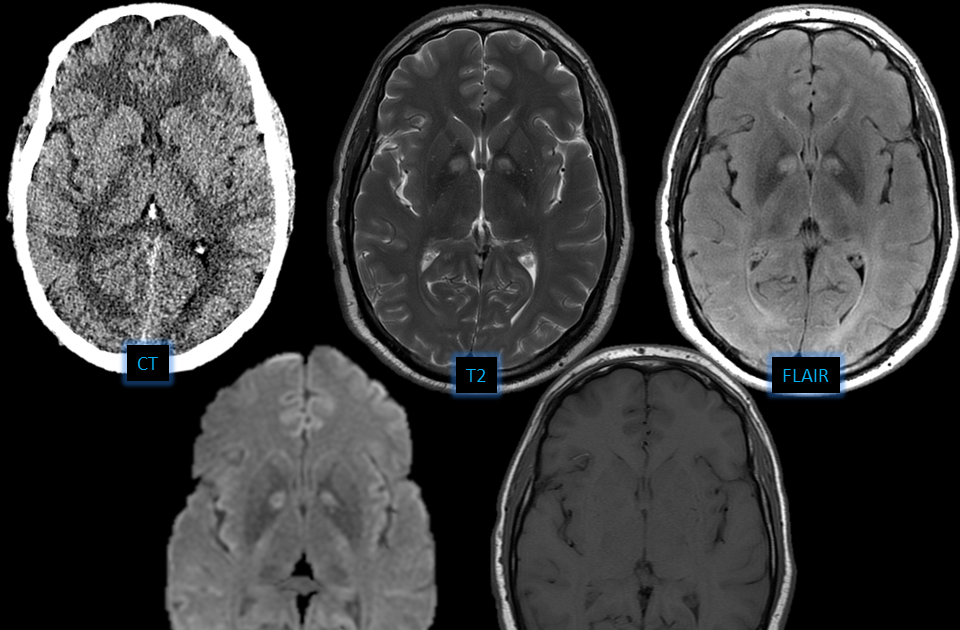

Показывает ли мрт наличие паразитов в организме - фото презентация